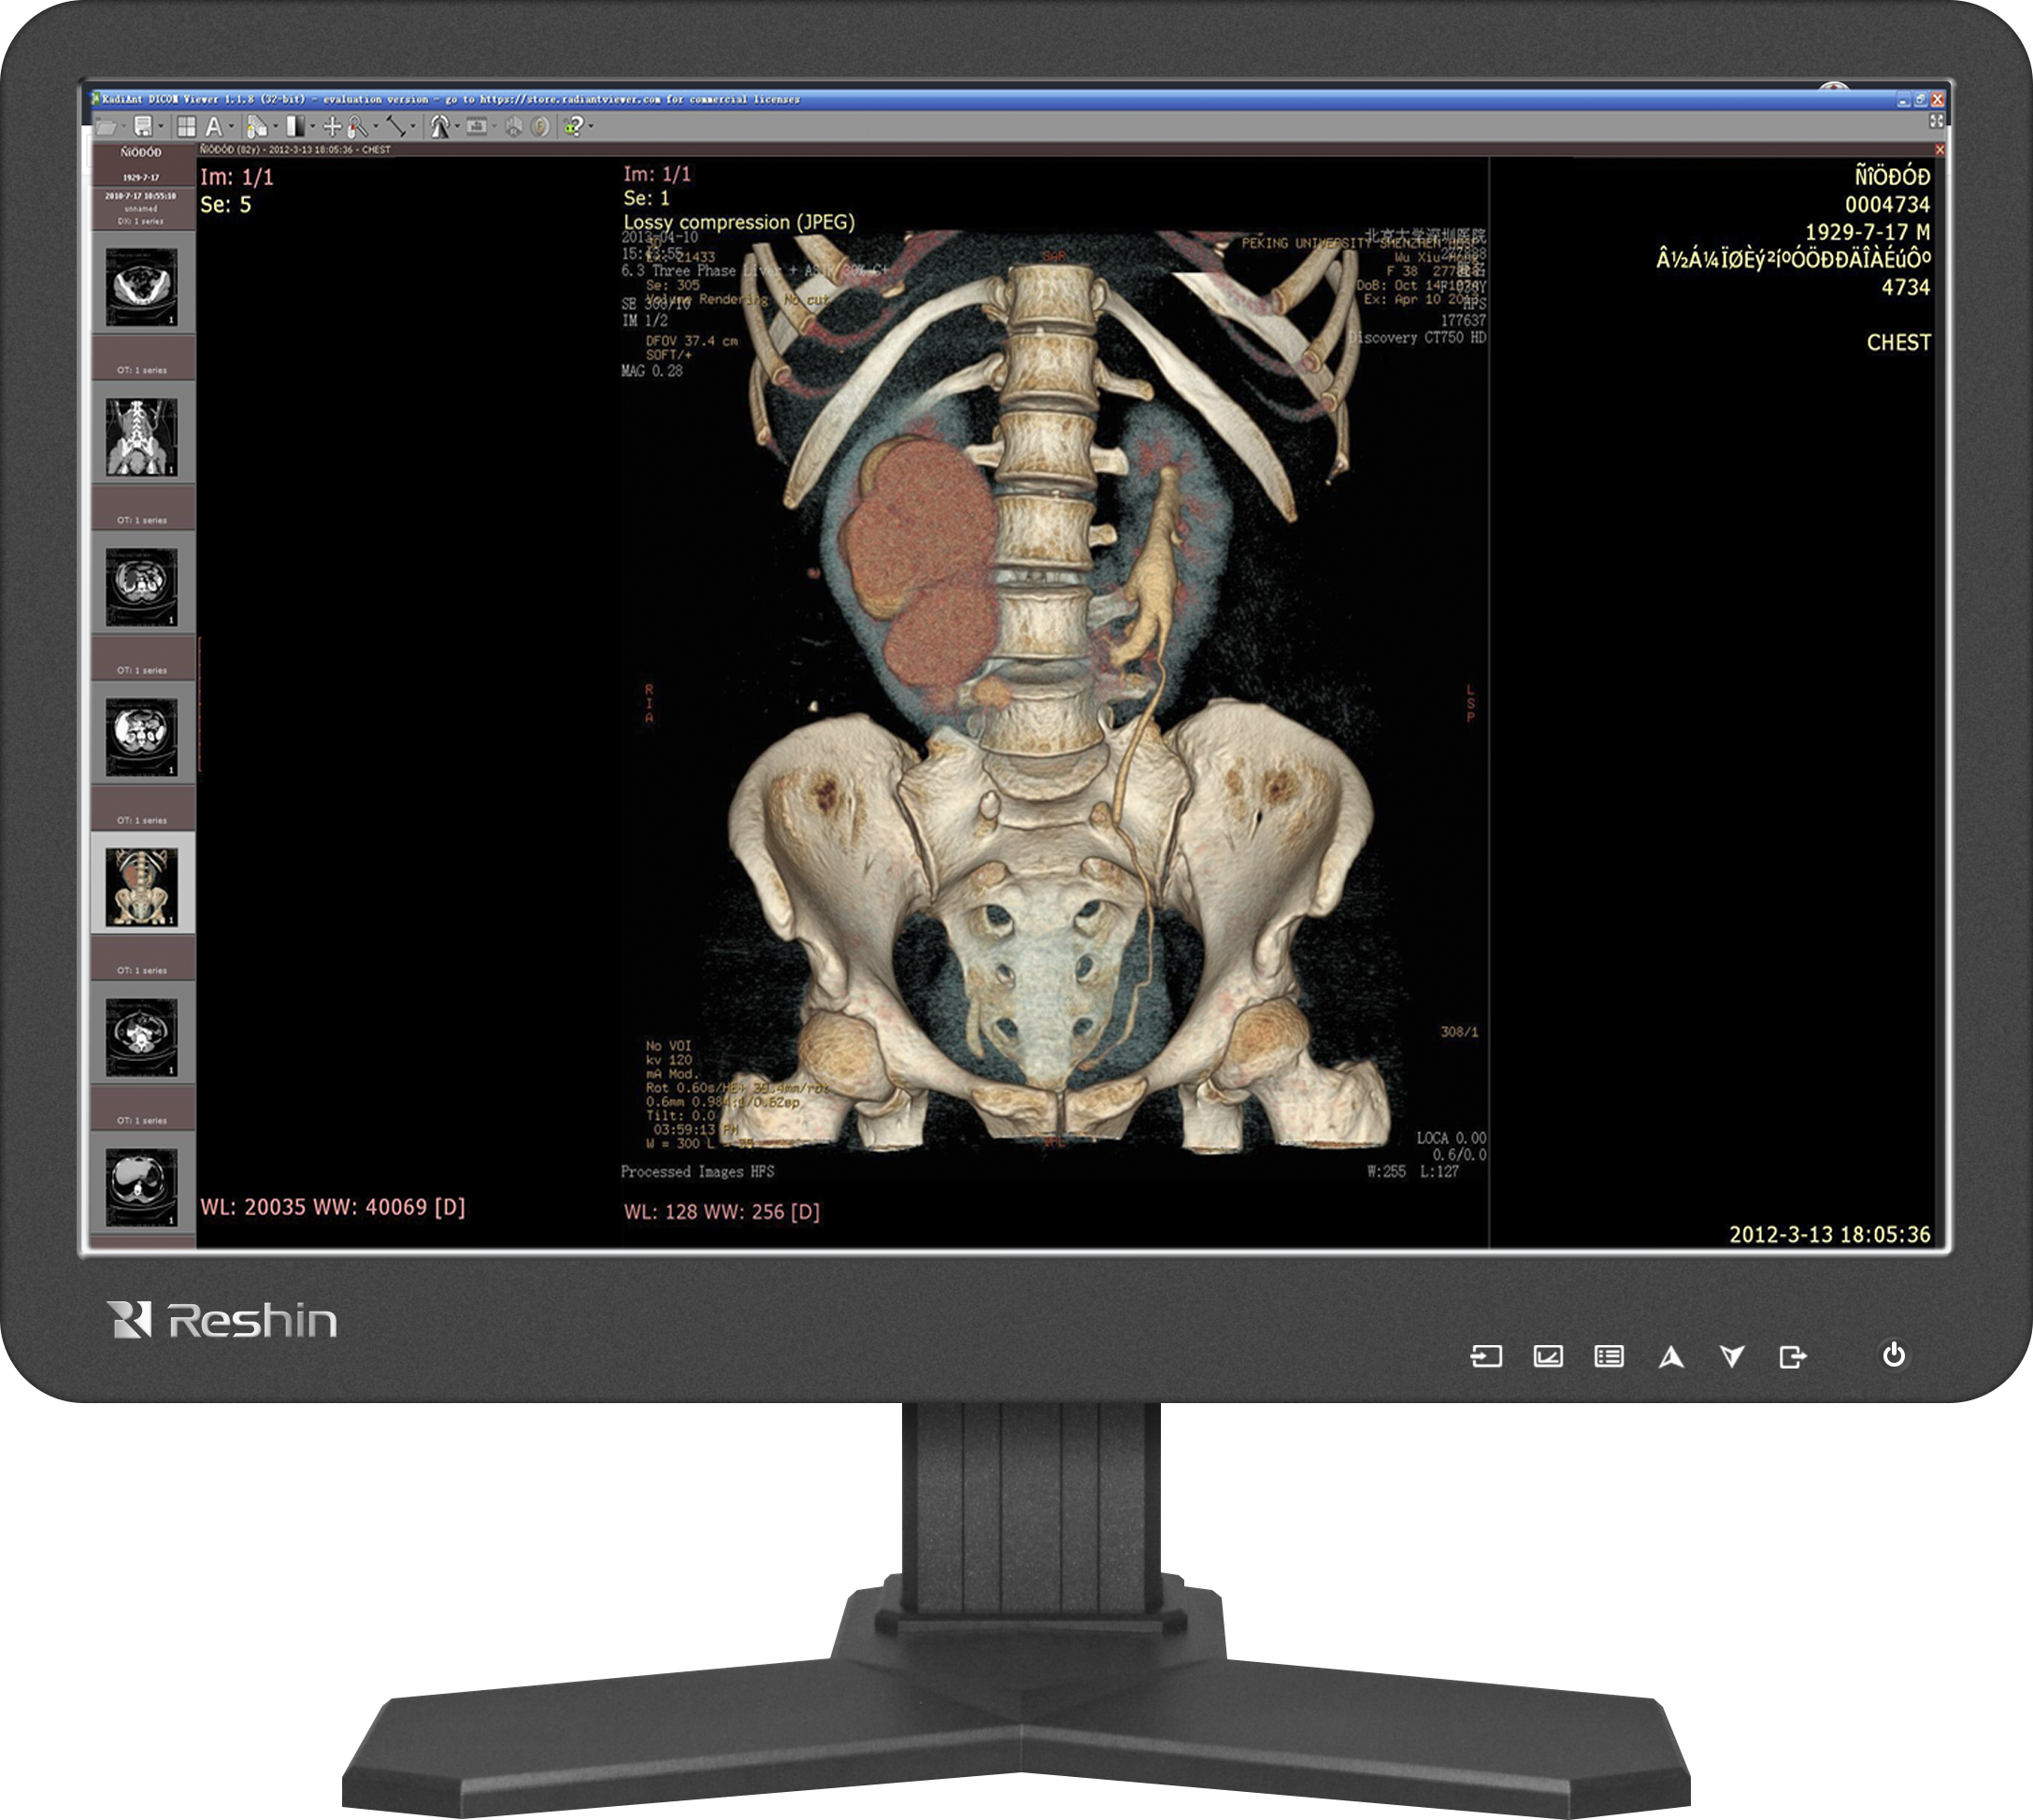

醫學影像診斷是臨床診療的關鍵環節之一。睿顯醫用顯示器憑借技術標準化、顯示精準化優勢,在教學中還原臨床真實影像細節,幫助學生逐步建立精準的診斷思維,為提升醫院服務質量注入動力。

DICOM標準的色域與亮度校準,能確保不同顯示器設備一致的影像效果,為醫院構建標準化教學體系提供硬件支撐。多模態顯示支持,靈活切換顯示不同類型的醫學影像(CT、MRI、超聲、內窺鏡等),并保證每類圖像的亮度、對比度、灰階都符合專業標準。